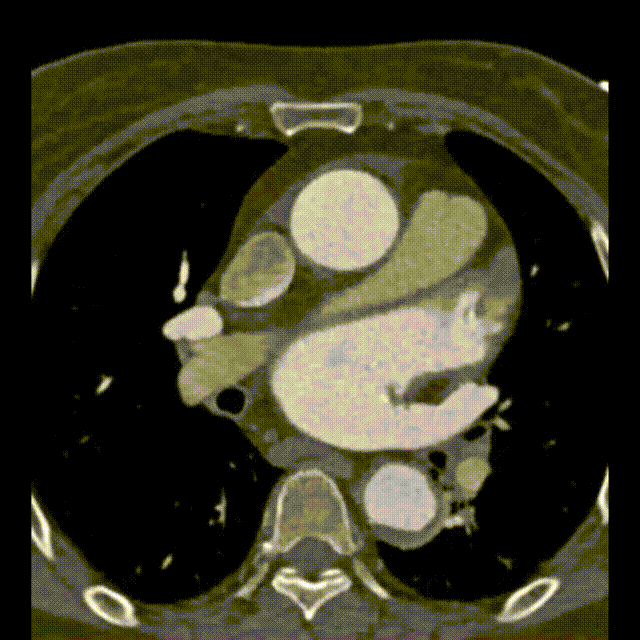

左心房CT显示,扩大的左心房内存在一个巨大的、光滑的、边界清楚的充盈缺损,与房间隔中部紧密相连。在舒张期,肿物位于二尖瓣口附近(图1B和视频)。

B 患者CT显示左心房内巨大的肿物(箭头所指为左心房内的肿物)。

根据超声心动图和CT结果,怀疑患者左心房内存在巨大黏液瘤。患者接受了左心房肿物切除术(图1C)。